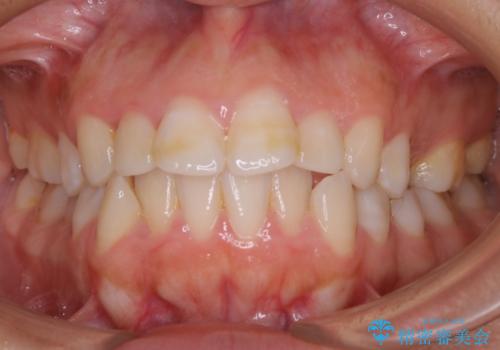

- 口元を下げたいという主訴でご来院されました。

ガタつきの度合いは軽度でしたが歯列の幅が狭く、その分前歯が上下とも前方に出てしまっていました。

しっかりと口元・顔貌まで変化を起こせるように上下左右の第一小臼歯を抜歯し、ワイヤー装置にて矯正を開始することとなりました。